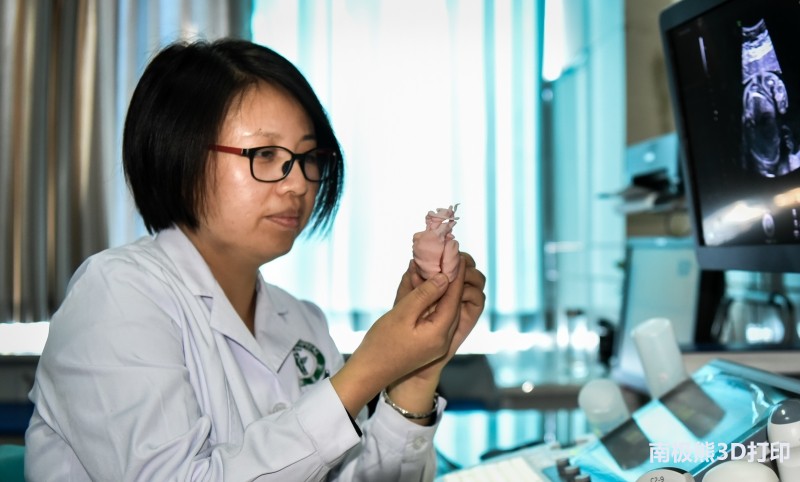

超声,作为一种无创且安全的检查手段,已广泛应用于孕期先天性心脏病的筛查工作中。唐都医院超声医学科配有先进的超声仪器设备,并有高资质的医师能够熟练掌握胎儿心脏二维及三维图像采集、分析及提取,所得到的图像数据完全符合三维重建的要求。另外,唐都医院超声医学科3D打印研究中心自2016年成立以来,先后完成了上百例人工骨替换物、血管外支架、骨骼及多种器官模型的建模打印,针对图像数据处理、建模及打印有着丰富的经验和完善的工作流程。

另外,由于超声影像图的读取需要读取者具有一定的医学专业背景,对于先心病的病患及其家属来说,仅从超声影像上理解胎儿的病情较为困难。有了3D打印的胎儿心脏模型,医生可以将个体胎儿心脏的模型拿在手上,与病患及其家属交流病情,帮助他们理解患儿的情况,增加病人对医生的信任度,从而有利于进行咨询。